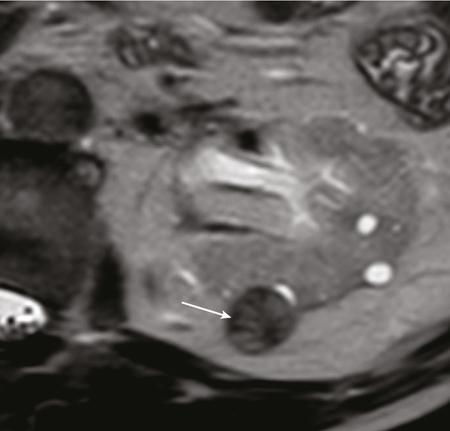

IMAGING OF RENAL MALIGNANCIES IN ADULTS Aparna Katdare, Palak Bhavesh Popat, Nilesh P. Sable, Ganesh Bakshi, Suyash Kulkarni Detection of renal masses has increased remarkably in recent times owing to wide-spread use of cross-sectional imaging. Imaging plays an important role in characterizing renal masses and is indispensable in treatment planning in renal malignancies. The most commonly encountered malignant renal masses in practice include renal cell carcinoma (RCC), urothelial carcinoma, lymphoma and metastases. Urothelial carcinoma and lymphoma have been covered in detail in separate chapters. RCC constitutes nearly 90% of all renal malignancies with a higher incidence in North America and Europe than India, Africa and China. With an increase in the number of cross-sectional studies performed, especially in Western population, the incidental diagnosis of RCC has increased in recent times, with such incidentally diagnosed lesions presenting at earlier stages with better prognosis and reduced rates of recurrence. The median age of presentation of RCC is 64 years according to the Surveillance, Epidemiology and End Results (SEER) program database and almost a decade earlier in Indian population, with a definite increasing risk of RCC with increasing age. Males are affected about 2–3.5 times more than females. In the Indian population, patients have been seen to present at a later stage as compared to the Western population. Amongst the various postulated risk factors, there is convincing evidence that smoking, hypertension, obesity and acquired renal cystic disease increase the risk of RCC. Alcohol intake and physical activity have been found to be associated with reduced risk of RCC. Trichloroethylene and cadmium exposure have been postulated as likely causes as well. Two to four per cent of RCCs are hereditary, with association of various genetic disorders such as Von Hippel Lindau (VHL) syndrome, hereditary papillary renal carcinoma, hereditary leiomyomatosis RCC, Birt-Hogg-Dube syndrome, chromosome 3 translocation and tuberous sclerosis (TCS1, TCS2). The WHO classification of 2016 (Table 11.25.1.1) stratifies tumours of the kidney into different subtypes based on cytoplasmic and architectural features, tumour location, background renal disease and molecular alterations. Clear cell renal cell carcinoma Multilocular cystic renal neoplasm of low malignant potential Papillary renal cell carcinoma Hereditary leiomyomatosis and renal cell carcinoma-associated renal cell carcinoma Chromophobe renal cell carcinoma Collecting duct carcinoma Renal medullary carcinoma MiT family translocation renal cell carcinomas Succinate dehydrogenase-deficient renal carcinoma Mucinous tubular and spindle cell carcinoma Tubulocystic renal cell carcinoma Acquired cystic disease-associated renal cell carcinoma Clear cell papillary renal cell carcinoma Renal cell carcinoma, unclassified Papillary adenoma Oncocytoma 8310/3 8316/1a 8260/3 8311/3* 8317/3 8319/3 8510/3a 8311/3a 8311/3 8480/3a 8316/3a 8316/3 8323/1 8312/3 8260/0 8290/0 Metanephric adenoma Metanephric adenofibroma Metanephric stromal tumour 8325/0 9013/0 8935/1 Nephrogenic rests Nephroblastoma Cystic partially differentiated nephroblastoma Paediatric cystic nephroma 8960/3 8959/1 8959/0 Clear cell sarcoma Rhabdoid tumour Congenital mesoblastic nephroma Ossifying renal tumour of infancy 8964/3 8963/3 8960/1 8967/0 Leiomyosarcoma Angiosarcoma Rhabdomyosarcoma Osteosarcoma Synovial sarcoma Ewing sarcoma Angiomyolipoma Epithelioid angiomyolipoma Leiomyoma Haemangioma Lymphangioma Haemangioblastoma Juxtaglomerular cell tumour Renomedullary interstitial cell tumour Schwannoma Solitary fibrous tumour 8890/3 9120/3 8900/3 9180/3 9040/3 9364/3 8860/0 8860/1a 8890/0 9120/0 9170/0 9161/1 8361/0 8966/0 9560/0 8815/1 Cystic nephroma Mixed epithelial and stromal tumour 8959/0 8959/0 Well-differentiated neuroendocrine tumour Large cell neuroendocrine carcinoma Small cell neuroendocrine carcinoma Phaeochromocytoma 8240/3 8013/3 8041/3 8700/0 Renal haematopoietic neoplasms Germ cell tumours The morphology codes are from the International Classification of Diseases for Oncology (ICD-O) {917A}, Behaviour is coded/0 for benign tumours; /1 for unspecified, borderline or uncertain behaviour; /2 for carcinoma in situ and grade III intraepithelial neoplasia; and /3 for malignant tumours. The classification is modified from the previous WHO classification (756A), taking into account changes in our understanding of these lesions. aNew code approved by the IARC/WHO Committee for ICD-O. Of these, the most common entity is the clear cell subtype, while papillary and chromophobe subtypes are less common. The different subtypes show varied biological behaviour, treatment response and prognosis. The 2017 guidelines by American Urological Association (AUA) as well as 2019 guidelines by European Society of Medical Oncology (ESMO) recommend multiphase cross-sectional imaging by either CT or MRI for renal mass characterization and staging. AUA 2017 guidelines recommend renal mass characterization on the basis of tumour complexity, contrast enhancement and presence or absence of fat. MRI has an upper hand over CT in characterizing subtle mass enhancement, cystic lesions and lesions less than 2 cm. ESMO recommends contrast-enhanced CT study of the chest, abdomen and pelvis for renal mass staging. Bone scan and brain CT or MRI can be considered if indicated by clinical or laboratory investigations. For characterization of renal masses, a multiphase CT or MRI study is recommended. CT study constitutes an unenhanced study followed by contrast injection and acquisition of corticomedullary phase at 40 seconds, nephrographic phase at around 100 seconds and delayed phase at around 5 minutes. MRI protocol includes T2-weighted single-shot fast spin-echo 2D sequences, axial T1-weighted 2D sequence with in-phase and opposed-phase gradient echo imaging, precontrast and postcontrast imaging with a 3D T1-weighted spoiled gradient recalled sequences in corticomedullary phase at 30 seconds, nephrographic phase at 100 seconds, 180–210 seconds and delayed phase imaging at 5 minutes and diffusion-weighted imaging with multiple b-values 0–50, 400–500 and 800–1000 s/mm2. The ACR White Paper on CT imaging of incidental renal mass recommends using the following descriptors for characterizing renal masses: Given the prognostic implications, it is worthwhile for radiologists to know the imaging features that may help discriminate between the common histological subtypes of RCC on various imaging modalities. This is the most common histological type of RCC, accounting for about 70% of cases. These are exophytic tumours with a heterogeneous appearance due to the presence of necrosis, intratumoural haemorrhage, cystic components with septations and calcific foci and hence have a more heterogeneous appearance on cross-sectional imaging than the other subtypes (Fig. 11.25.1.1). Necrosis is seen more often in larger masses and higher tumour grades (Fig. 11.25.1.2). On CT, depending on the tumour composition, these are seen as heterogeneous lesions, show marked contrast enhancement in the corticomedullary phase with washout on nephrogenic phase (Fig. 11.25.1.2). On MRI, these characteristically show high signal intensity on T2W sequences (Fig. 11.25.1.3). The presence of intracytoplasmic fat in the clear cells of the tumour is reflected in the loss of signal in opposed phase images on chemical shift imaging, which is seen in nearly 60% of these tumours. A pseudocapsule may be seen, which is best appreciated on T2-weighted imaging on MRI; the presence of a pseudocapsule has a high negative predictive value for perinephric extension (Figs. 11.25.1.3 and 11.25.1.4). Conversely, larger tumours with higher grades often have interrupted pseudocapsule and hence tend to be irregular, spread into the perinephric fat with renal vein and inferior vena cava (IVC) invasion (Figs. 11.25.1.5 and 11.25.1.6). On diffusion-weighted imaging, clear cell RCCs have been seen to have higher ADC values than nonclear cell RCCs, and lower-grade tumours have been seen to have higher ADC values than higher-grade tumours. The clear cell variant has worse prognosis than the papillary and chromophobe subtypes, presenting at a more advanced stage and being more likely to recur or metastasize (Fig. 11.25.1.7), with lower 5-year survival rates at 44%–69% as compared to 78%–92% for the other two. Papillary RCC comprises about 10%–15% of RCCs. These are slow-growing tumours and hence are well-marginated in contrast to clear cell RCC. As they are hypovascular, their enhancement on CT is significantly less than clear cell RCC (Fig. 11.25.1.8). These show characteristically low signal on T2W images on MRI (Fig. 11.25.1.9). Intracytoplasmic or macroscopic fat is less often seen on MRI imaging as compared to the clear cell variants. Larger tumours tend to be more heterogeneous (Fig. 11.25.1.10). These tumours may sometimes show cystic appearances, mural projections or blood degradation products. Calcifications are more common in papillary variants than clear cell RCC. Multifocality and bilaterality are also more common in these tumours than clear cell variants. These account for about 5% of RCCs. These are less aggressive, more homogeneous and hypovascular lesions than clear cell variants, with intensity of contrast enhancement on cross-sectional imaging being midway between clear cell and papillary variants. They show low to intermediate T2 signals on MRI. A characteristic feature is the presence of a central scar and spoke-wheel enhancement, the latter being a histopathological and imaging similarity between these tumours and oncocytoma (Fig. 11.25.1.11). Other subtypes of RCC are much less common but some may show distinct imaging findings. Multilocular cystic RCCs have excellent prognosis and lack mural nodules within the cystic components, unlike clear cell RCCs with cystic degeneration which show mural nodules. Collecting duct carcinomas, on the other hand, are aggressive tumours with poor prognosis and have medullary origin, and therefore appear similar to transitional cell carcinomas on imaging. Medullary RCCs are associated with sickle cell disease and sickle cell trait and are seen as infiltrating intracalyceal obstructive lesions with associated nodal disease. The imaging work-up of a suspected RCC is aimed at: Localized renal cancer is defined as a disease confined to the renal capsule and refers mainly to stage I and II disease. Nearly 70% of RCCs, especially the lower-stage lesions, are incidentally diagnosed on cross-sectional imaging. Also, amongst incidentally diagnosed renal lesions less than 4 cm in size, about 20% turn out to be benign on histopathology. Asymptomatic incidentally diagnosed small renal masses have an indolent course and better prognosis. Nephron-sparing surgery (NSS) has gathered momentum in recent years due to promising results and prognoses in small lesions. The 2017 AUA guidelines for localized renal masses describe restricted and well-defined indications for radical nephrectomy, bigger role of nephron-sparing procedures such as partial nephrectomy, tumour enucleation and thermal ablation, as well as increasing role for biopsy as well as active surveillance of such lesions. Hence, imaging findings in these lesions become critical in charting management of these patients. The imaging features of common histopathological subtypes of RCCs have already been discussed above. Signal intensity on T2W images and corticomedullary phase enhancement have been seen to be independent predictors of clear cell and papillary RCCs. Further, T2 signal homogeneity can be a predictor for slower growth rate. Hence, in general, multiparametric MRI studies have been shown to be effective in small renal mass characterization and can subsequently guide decisions regarding biopsy, surgery or surveillance. CT is a good alternative in patients with contraindication to MRI. For cystic renal lesions, the Bosniak classification, which stratifies the risk of neoplasia in cystic renal lesions based on the complexity of their appearance (wall thickness, septations, solid component), can be used effectively to decide further course of management. The Bosniak classification originally applies to CT findings but can logically be extrapolated to MRI, USG and Contrast Enhanced Ultrasound (CEUS) as well. Bosniak I and II cysts are benign while Bosniak IIF, III and IV cysts show progressively increasing risk of neoplasia. Given the more indolent course of cystic RCCs as compared to solid lesions and possible complications of interventions, lately there has been a case for even the type III and IV cysts, which previously would be operated, to be followed up, especially if patient has existing comorbidities or if the solid component is minimal. Initial follow-up would be at 6 months, followed by annual imaging. AUA 2017 guidelines recommend considering renal mass biopsy if haematologic, metastatic, inflammatory or infectious aetiology is suspected. Once the need for surgery is established in a localized disease, NSS may be considered for stage Ia and Ib disease. To predict perioperative outcomes in NSS, various scoring systems have been proposed for preoperative renal mass evaluation, such as R.E.N.A.L. nephrometry score, PADUA score (Preoperative aspects and dimensions used for anatomical classification), C-index method and mathematical tumour contact surface area (CSA). The popular R.E.N.A.L. nephrometry score takes into account various tumour descriptors that help decide the technical feasibility of NSS and predict surgical outcomes. These include tumour radius, exo/endophytic location, nearness to collecting system or renal sinus, anterior/posterior location and location with reference to polar lines. These descriptors need to be commented upon diligently while reporting renal masses (Table 11.25.1.4). Higher scores are seen to correlate with ischaemia time, postoperative urologic complications, higher grade and mortality. These include organ-confined tumours more than 7 cm in size, or tumours of any size which show regional nodal involvement and/or invasion of perinephric tissues but confined to Gerota’s fascia. These include renal vein and IVC invasion (luminal and mural). Generally, radical nephrectomy is recommended by the National Comprehensive Cancer Network (NCCN) in stage II and III RCCs. Both CT and MRI are effective in diagnosing locally advanced disease in RCC. The loss or interruption of pseudocapsule is seen in more infiltrative and aggressive disease and is best seen on MRI. Local infiltration may be in the form of contiguous spread to perinephric tissues or discrete deposits in perinephric fat (Fig. 11.25.1.15). IVC or renal vein invasion could be in the form of intraluminal thrombosis or invasion of the vessel wall and have implications on surgical approach and outcomes. Tumour thrombus can be distinguished from bland thrombus by confirming vascularity within the thrombus on imaging. Doppler evaluation, CEUS, CT and MRI can all be helpful for the same. MRI is better than other modalities for venous evaluation, especially for mural invasion and IVC invasion (Figs. 11.25.1.16 and 11.25.1.17). Right-sided tumours, anteroposterior IVC diameter of 2.4 cm or more at the level of renal hilum and complete IVC occlusion at this level are associated with higher risk of IVC resection. About 16% of patients with RCC have metastases at diagnosis and about 20%–30% of patients operated for local disease develop recurrence or metastases at a later date. The recurrent disease occurs most commonly within 3 years of diagnosis and uncommonly even later in young patients or large tumours. The most common sites of metastases from RCC are lungs, liver, bones, nodes, adrenals and brain. CT scan is the preferred modality for primary staging and surveillance for metastases because of its widespread availability and versatility for diagnosing bone and soft tissue lesions. MRI is preferred for looking for recurrence in postablative lesions, wherein these are seen as new enhancing lesions or show increase in the size of preexisting enhancing components. 18FFluorodeoxyglucose – Positron Emission Tomography (PET)/CT and PET/MRI may be helpful to look for metastatic disease as well. 18FSodium fluoride – PET/CT has been found to be better than CT and bone scan in detecting osseous metastases. RCC is a relatively radiation-resistant tumour, and treatment options tilt in favour of surgical procedures for localized and locally advanced diseases. For metastatic disease, post-risk assignment, the treatment has to be planned. Treatment can be offered as per size and the clinical stage.